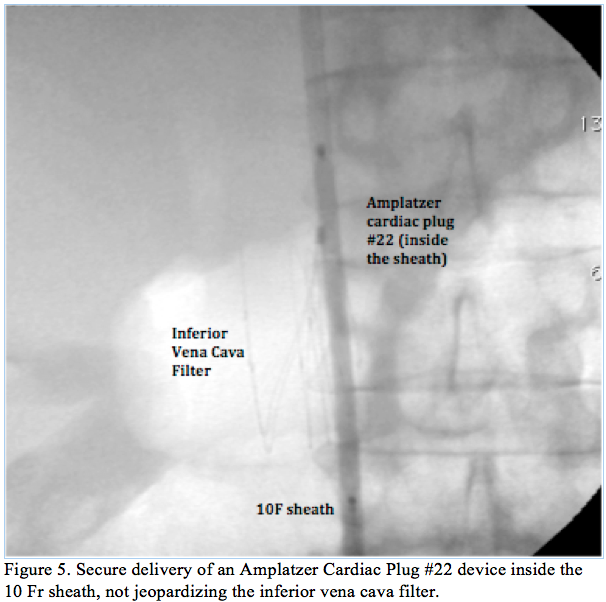

Procedure 2. Right femoral venous access was obtained and contrast media was injected to confirm the patency and absence of thrombus on the IFCV. A very-soft 0.035˝ wire (Benson wire, Parkmore Business) crossed the IVCF, over which a 6 Fr catheter was advanced, allowing the exchange for a stiff wire. A large, 90 cm, 10 Fr sheath was inserted and positioned in the right

atrium, crossing uneventfully through the IVCF (Figure 4). The Amplatzer releasing system was delivered to the right atrium via the large, 90 cm, 10 Fr sheath positioned through the IVCF, avoiding further manipulation at the level of the IVCF (Figure 5). Standard left atrial appendage closure was performed with an Amplatzer Cardiac Plug (ACP) #22 device (AGA Medical Corporation). Using the same releasing system, a #25 Amplatzer device for PFO closure was successfully implanted (AGA Medical Corporation). Continuous monitoring of the procedure with transesophageal echocardiography was performed and the correct deployment of both devices was secured (Figure 6). Careful x-ray guided retrieval of the